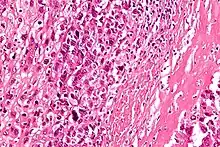

Au microscope la caractéristique de l'ostéosarcome est la présence d'ostéoïde (formation osseuse) dans la tumeur. Les cellules tumorales sont très pléomorphes (anaplasiques), certaines sont géantes, et de nombreuses mitoses sont atypiques. Ces cellules produisent des ostéoïdes décrivant des travées irrégulières (amorphes, éosinophiles / roses) avec ou sans calcification centrale (hematoxylinophilic / bleu, granulaire) - os de la tumeur. Les cellules tumorales sont incluses dans la matrice ostéoïde. Les ostéosarcomes peuvent présenter des cellules géantes ostéoclastiques comme multinucléées[7].

Selon les caractéristiques des cellules tumorales présentes (qu'elles ressemblent à des cellules osseuses, à des cellules cartilagineuses ou des cellules de type fibroblaste), la tumeur peut être classée en trois sous-types d’ostéosarcomes dit conventionnels de haut grade (75 % à 80 % des plus fréquents dans le cancer pédiatrique)[8] :

- ostéosarcome ostéoblastique : 70 %, majoritaire ; les cellules ostéoblastiques produisent une matrice ostéoïde immature. En condition physiologique, cette matrice se minéralise et donne lieu à l’apparition d’un os. Au contraire, lors de cancer des os, cette matrice n’a pas le temps de se minéraliser et donc de durcir ;

- ostéosarcome chondroblastique : 12 % ;

- ostéosarcome fibroblastique : 10 %.